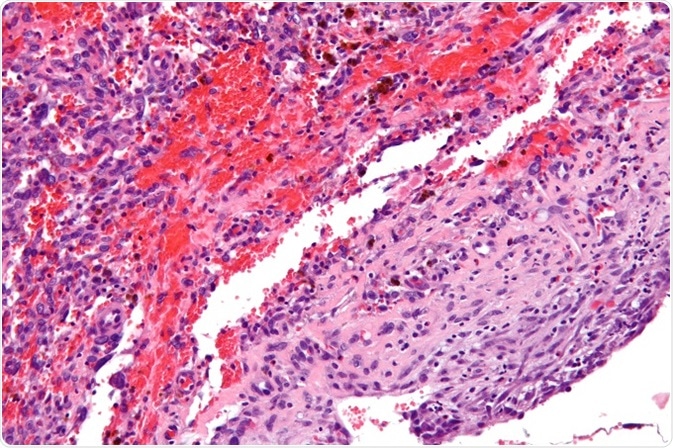

High magnification micrograph of an angiomatoid fibrous histiocytoma, H&E stain. ©Nephron/ commons.wikimedia.org.

The histopathologic features include hyperplasia of the epidermis and basal cell hyperpigmentation layer, which is called the ‘dirty fingernail’ sign. The tumor is in the dermis and is non-encapsulated. Whorls of spindle cells will be seen. However, several histological variants do occur, including cellular, aneurysmal, atrophic, and atypical dermatofibroma.